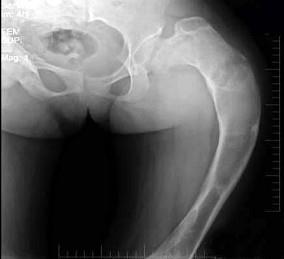

问题 17岁,女性患者左髋关节酸胀不适半年,骨盆正位片示左股骨上段骨质改变,最可能的诊断是 ( )

选项 A、骨斑点症 B、以上都不是 C、内生软骨瘤 D、骨纤维结构不良 E、骨髓炎

答案 D